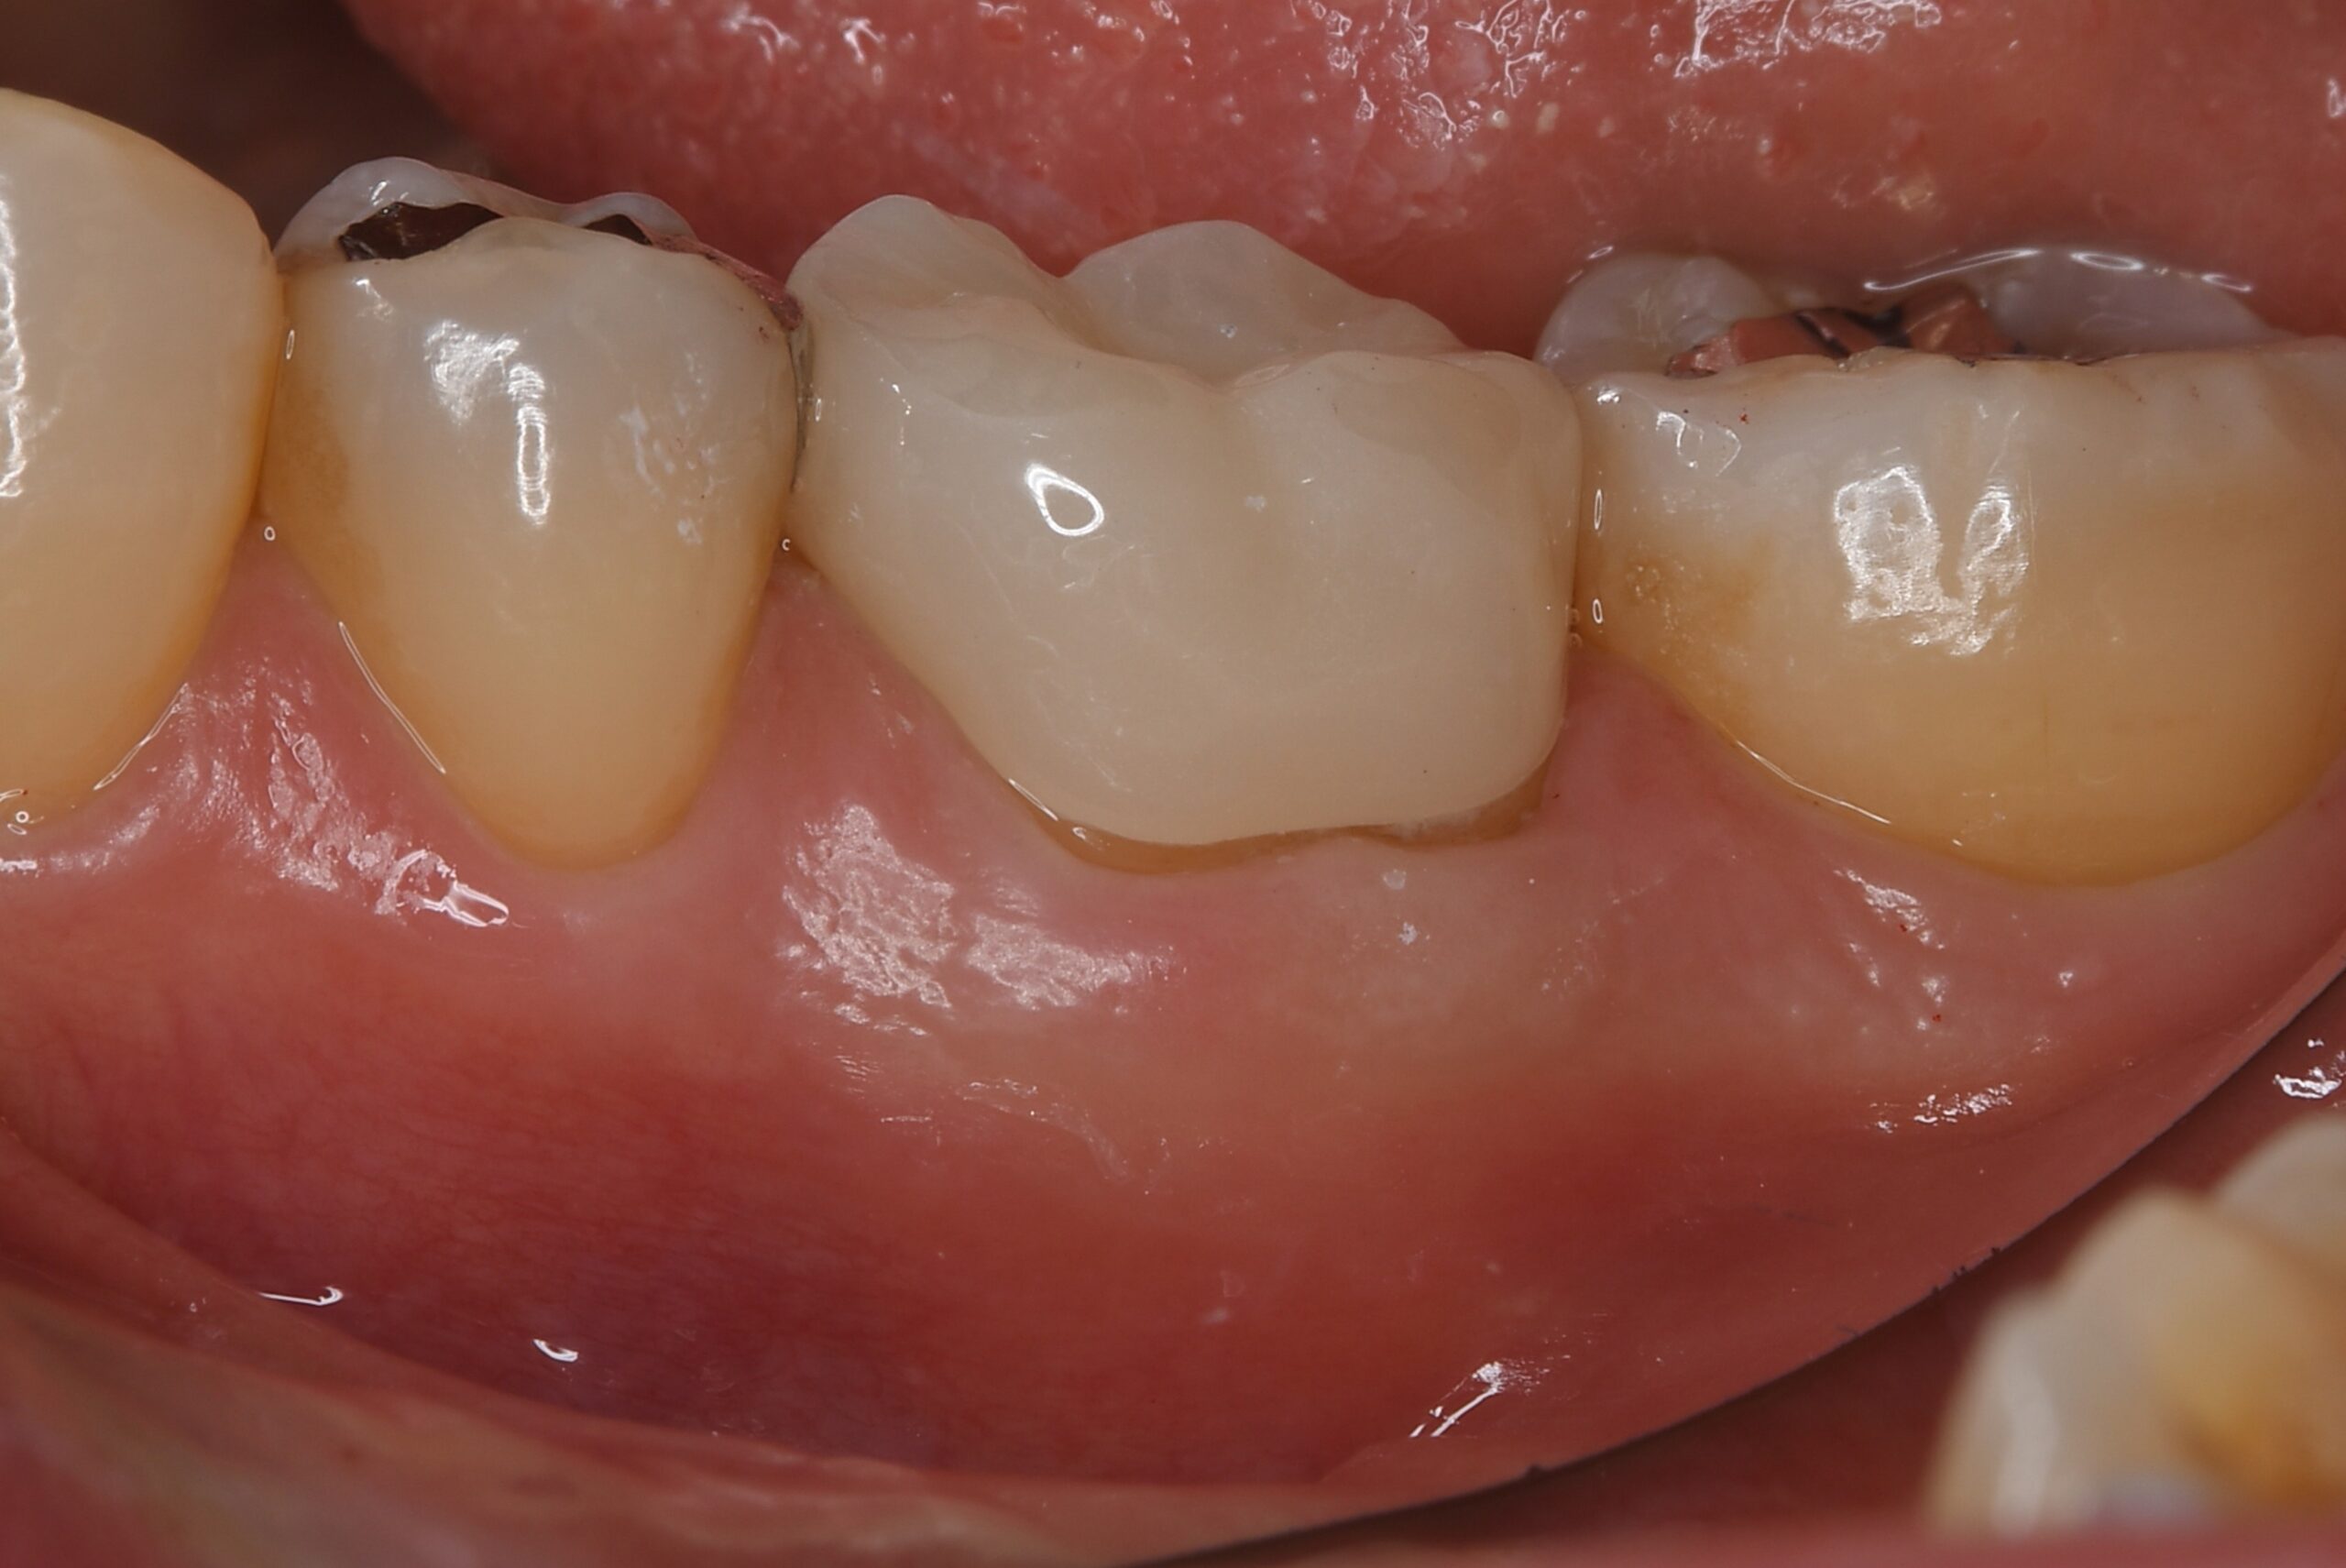

症例3

| 項目 | 詳細 |

|---|---|

| 患者様データ | 50代 女性 |

| 来院時の主訴 | 「左下の歯茎が腫れている。」 |

| 医院の診断 | 慢性根尖性歯周炎 |

| 通院期間 | 4ヶ月 |

| 来院回数 | 6回(定期的なチェック含む) |

| 治療費 | 220,000円(税抜) 《内訳》 精密根管治療80,000円、ファイバーポストコア20,000円、セラミック治療120,000円 |

| リスクと副作用 | ①根管治療歯は長期的には破折するリスク ②メインテナンスが必要 |

| ココがこだわりのポイント☝ |

ラバーダム防湿とマイクロスコープを使用して丁寧に治療を行いました。 |